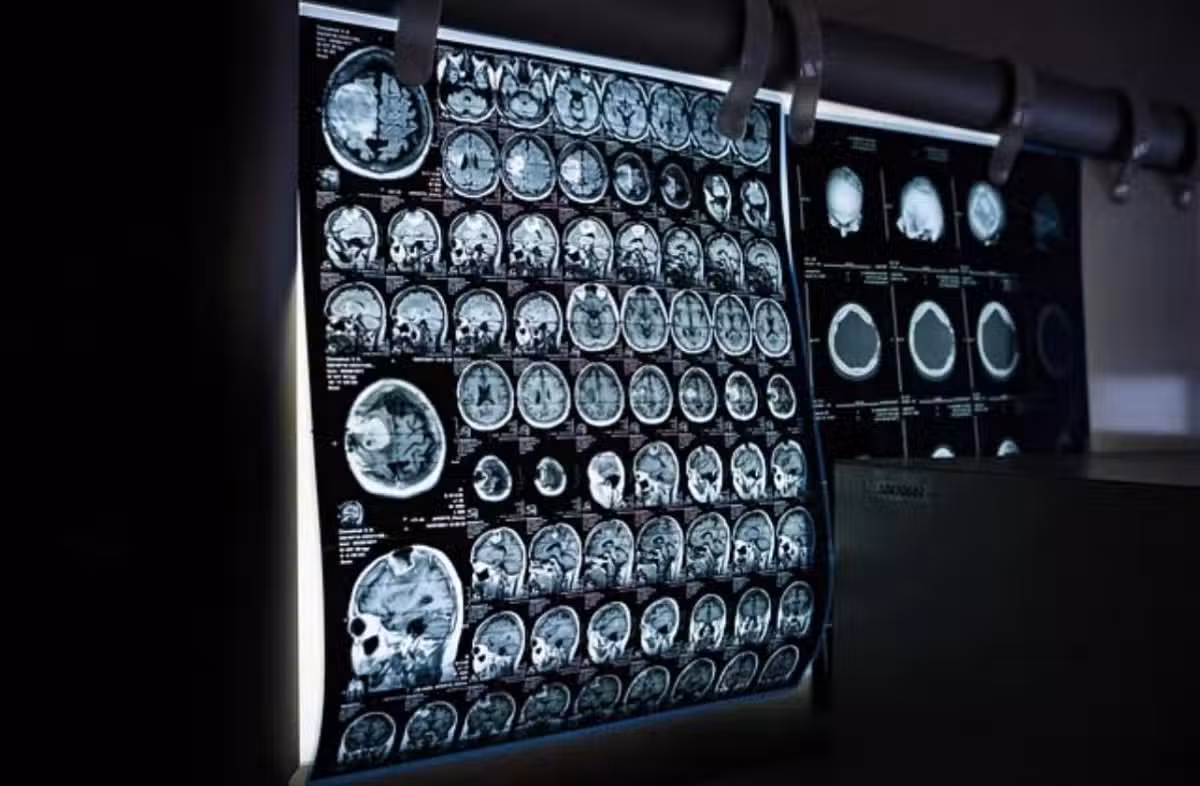

圖/翻攝自洪永祥醫師臉書

通常做電腦斷層或心導管、血管攝影等檢查,都需要靜脈注射顯影劑,注入體內後需要腎臟代謝,會造成血管收縮使得腎臟短暫的缺血性變化。通常腎功能正常的人不會有太大的影響,但慢性腎衰竭的患者則務必要小心,傷害會在注射後1~2天內出現,腎功能指數最高落在3~5天,通常1-2週內會自行恢復,但有部分四五期的患有,一次一次的注射導致急性腎損傷,尿毒症狀大爆發就開始洗腎。

洪永祥表示,若有住院的人在注射前一天,就可以前一天開始靜脈點滴輸液,連續2-3天增加腎臟灌流量,而非住院的患者也可以透過多喝水來取代,不過這樣的方法僅限於「水分還能排出腎、沒有水腫」的腎友,若已有嚴重積水或心臟衰竭者,可是反而會導致急性肺水腫,提早步入洗腎。